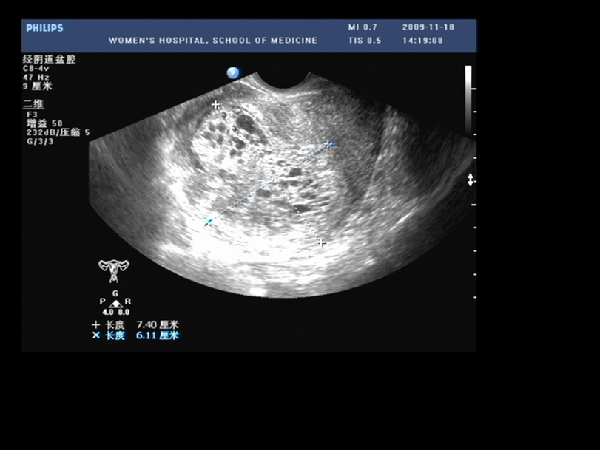

(5)婦科超聲:超聲下完全性葡萄胎的水泡呈"蜂窩狀"改變或"落雪征",多數患者的血HCG值比正常妊娠高。而部分性葡萄胎的水泡不明顯,HCG值升高不明顯,和普通的胚胎不發育相似,容易漏診,需要通過病理檢測。